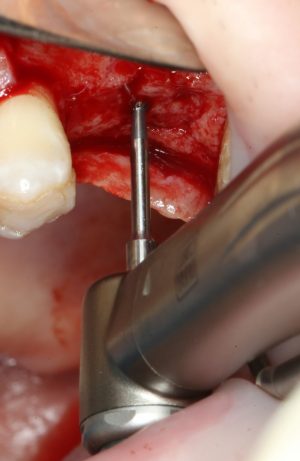

Далее, мы проходим лунку на всю глубину пилотной фрезой диаметром 2.0 мм.

После этого можно поставить пин и проверить направление и ангуляцию оси будущего имплантата.

Кстати, о пинах. В Astra Tech они, сцуко, хитрые. Диаметр тонкого конца 2.0 мм, а толстого — 3.2 мм. Это значит, что измерить и оценить ось имплантата мы можем на этапе пилотной фрезы (2.0 мм) и следующей за ней «зеленой» (3.2 мм). Далее точные изменения становятся невозможными. Платформа-ограничитель имеет размеры 3.5 (по узкой) и 5.0 (по широкой частям) мм, что позволяет оценить положение будущей лунки относительно других имплантов и соседних зубов в окклюзионной плоскости.

Следующей мы используем фрезу 2.0/3.2:

Такие фрезы — особенность имплантационной системы Astra Tech. Они нужны для того, чтобы не разломать края лунки и сделать переход между фрезами (а мы переходим с 2.0 на 3.2 мм) более точным и плавным, благодаря направляющей 2.0 мм. Однако, пройти лунку такой фрезой на всю глубину удаётся далеко не всегда. В таких случаях используется обычная спиральная фреза диаметром 3.2 мм (с зеленой полоской). Но в нашем случае такой необходимости нет, ибо выше только субантральное пространство, поэтому мы работаем только вот такой двойной фрезой.

После этого можно еще раз (последний, кстати), проверить направление и ангуляцию оси будущего имплантата. Всё тем же вышеозначенным пином: